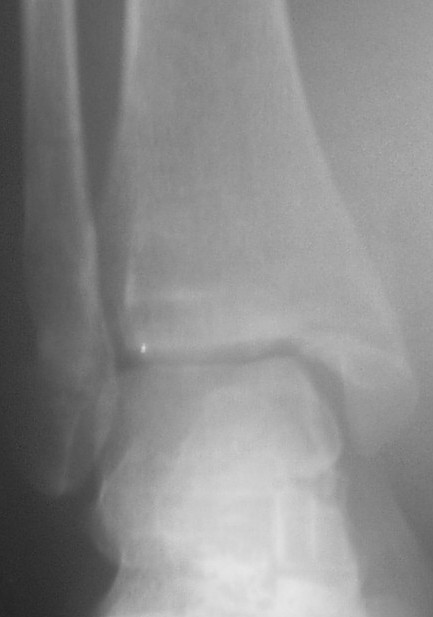

Прямой контрлатеральный сустав.JPG